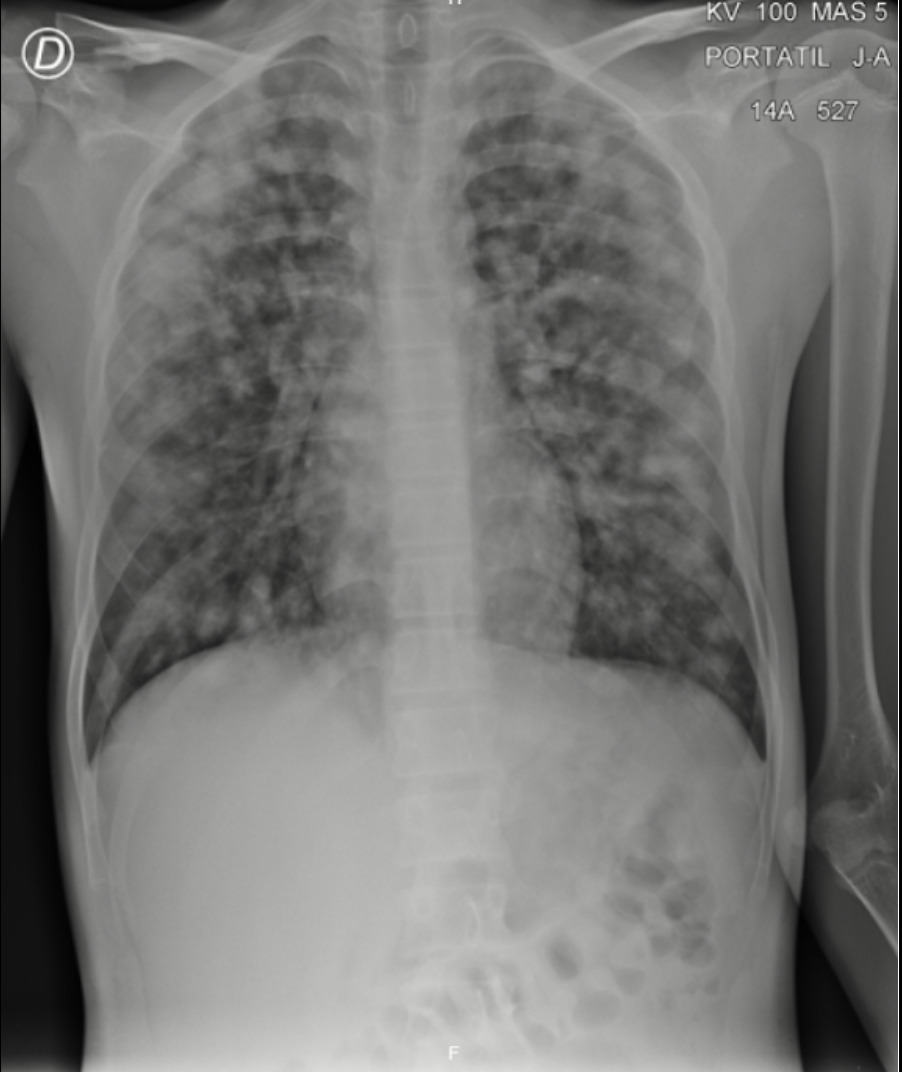

El paciente refiere adecuada evolución clínica por lo que se decidió iniciar pasó de respiración asistida con cánula nasal a bajo flujo a respiración espontánea sin dispositivo, la cual fue adecuadamente tolerada por el paciente y se solicitó nueva radiografía de tórax anteroposterior y lateral donde se evidencio normalidad por lo que se decidió dar egreso hospitalario al paciente con signos de alarma, recomendaciones, consulta de control y formula médica. Paciente y familiares refirieron estar de acuerdo

En los niños, la EPA se presenta como un aumento de la dificultad respiratoria durante uno o dos días, pero como en este caso, puede desarrollarse de manera precipitada. Los niños más pequeños pueden manifestar únicamente palidez o cianosis con afección del nivel de consciencia, sin embargo, la gran mayoría va a presentar taquipnea, hipoxemia y crépitos pulmonares (11). Es importante tener en cuenta el diagnóstico diferencial de este cuadro clínico, por lo que se hace importante mencionar que el EPA no provoca aumento de la temperatura, por lo que lo hace un signo indispensable al momento de realizar el diagnóstico, al igual que como ya se mencionó el periodo de aparición es agudo, al igual que los antecedentes inmunológicos del paciente, por lo que el diagnóstico debe ser individualizado (Ver figura 3).

Figura 3. Exploración radiológica al finalizar el manejo.